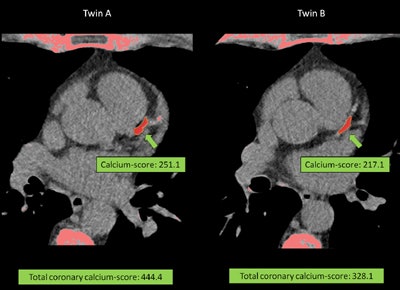

They used a semiautomated Agatston score to determine calcified plaque burden in each individual from native CT scans, and the group also calculated a segment involvement score (SIS), representing the total number of segments with plaque. The segment stenosis score (SSS) was used to represent the sum of all stenoses, including minimal = 1, mild = 2, moderate = 3, and severe = 4. Finally, the SSS index (SSSi) was used to represent the SSS/total segment number, while the SIS index (SISi) represents the SIS/total segment number, the authors wrote in an abstract.

As for the Falconer-scale based heritability of coronary artery plaque however, MZ versus DZ showed important differences in calcified plaque burden depending on twin type, 0.71 versus 0.21, with monozygotic twins tending to have very similar calcified plaque burdens, while total plaque burdens -- mostly representing noncalcified plaques -- were not correlated with twin type.

Calcium score | 0.71 | 0.21 | 1.015 |

The results showed that calcified plaque burden has stronger heritability than total plaque burden, Maurovich-Horvat said. And because the influence of the environment in total plaque burden is driven mainly by noncalcified plaque burden, the good news is that lifestyle changes and medication can potentially change the outcomes of twins with noncalcified plaques. The process does need some improving, and more twin pairs need to be studied, however.